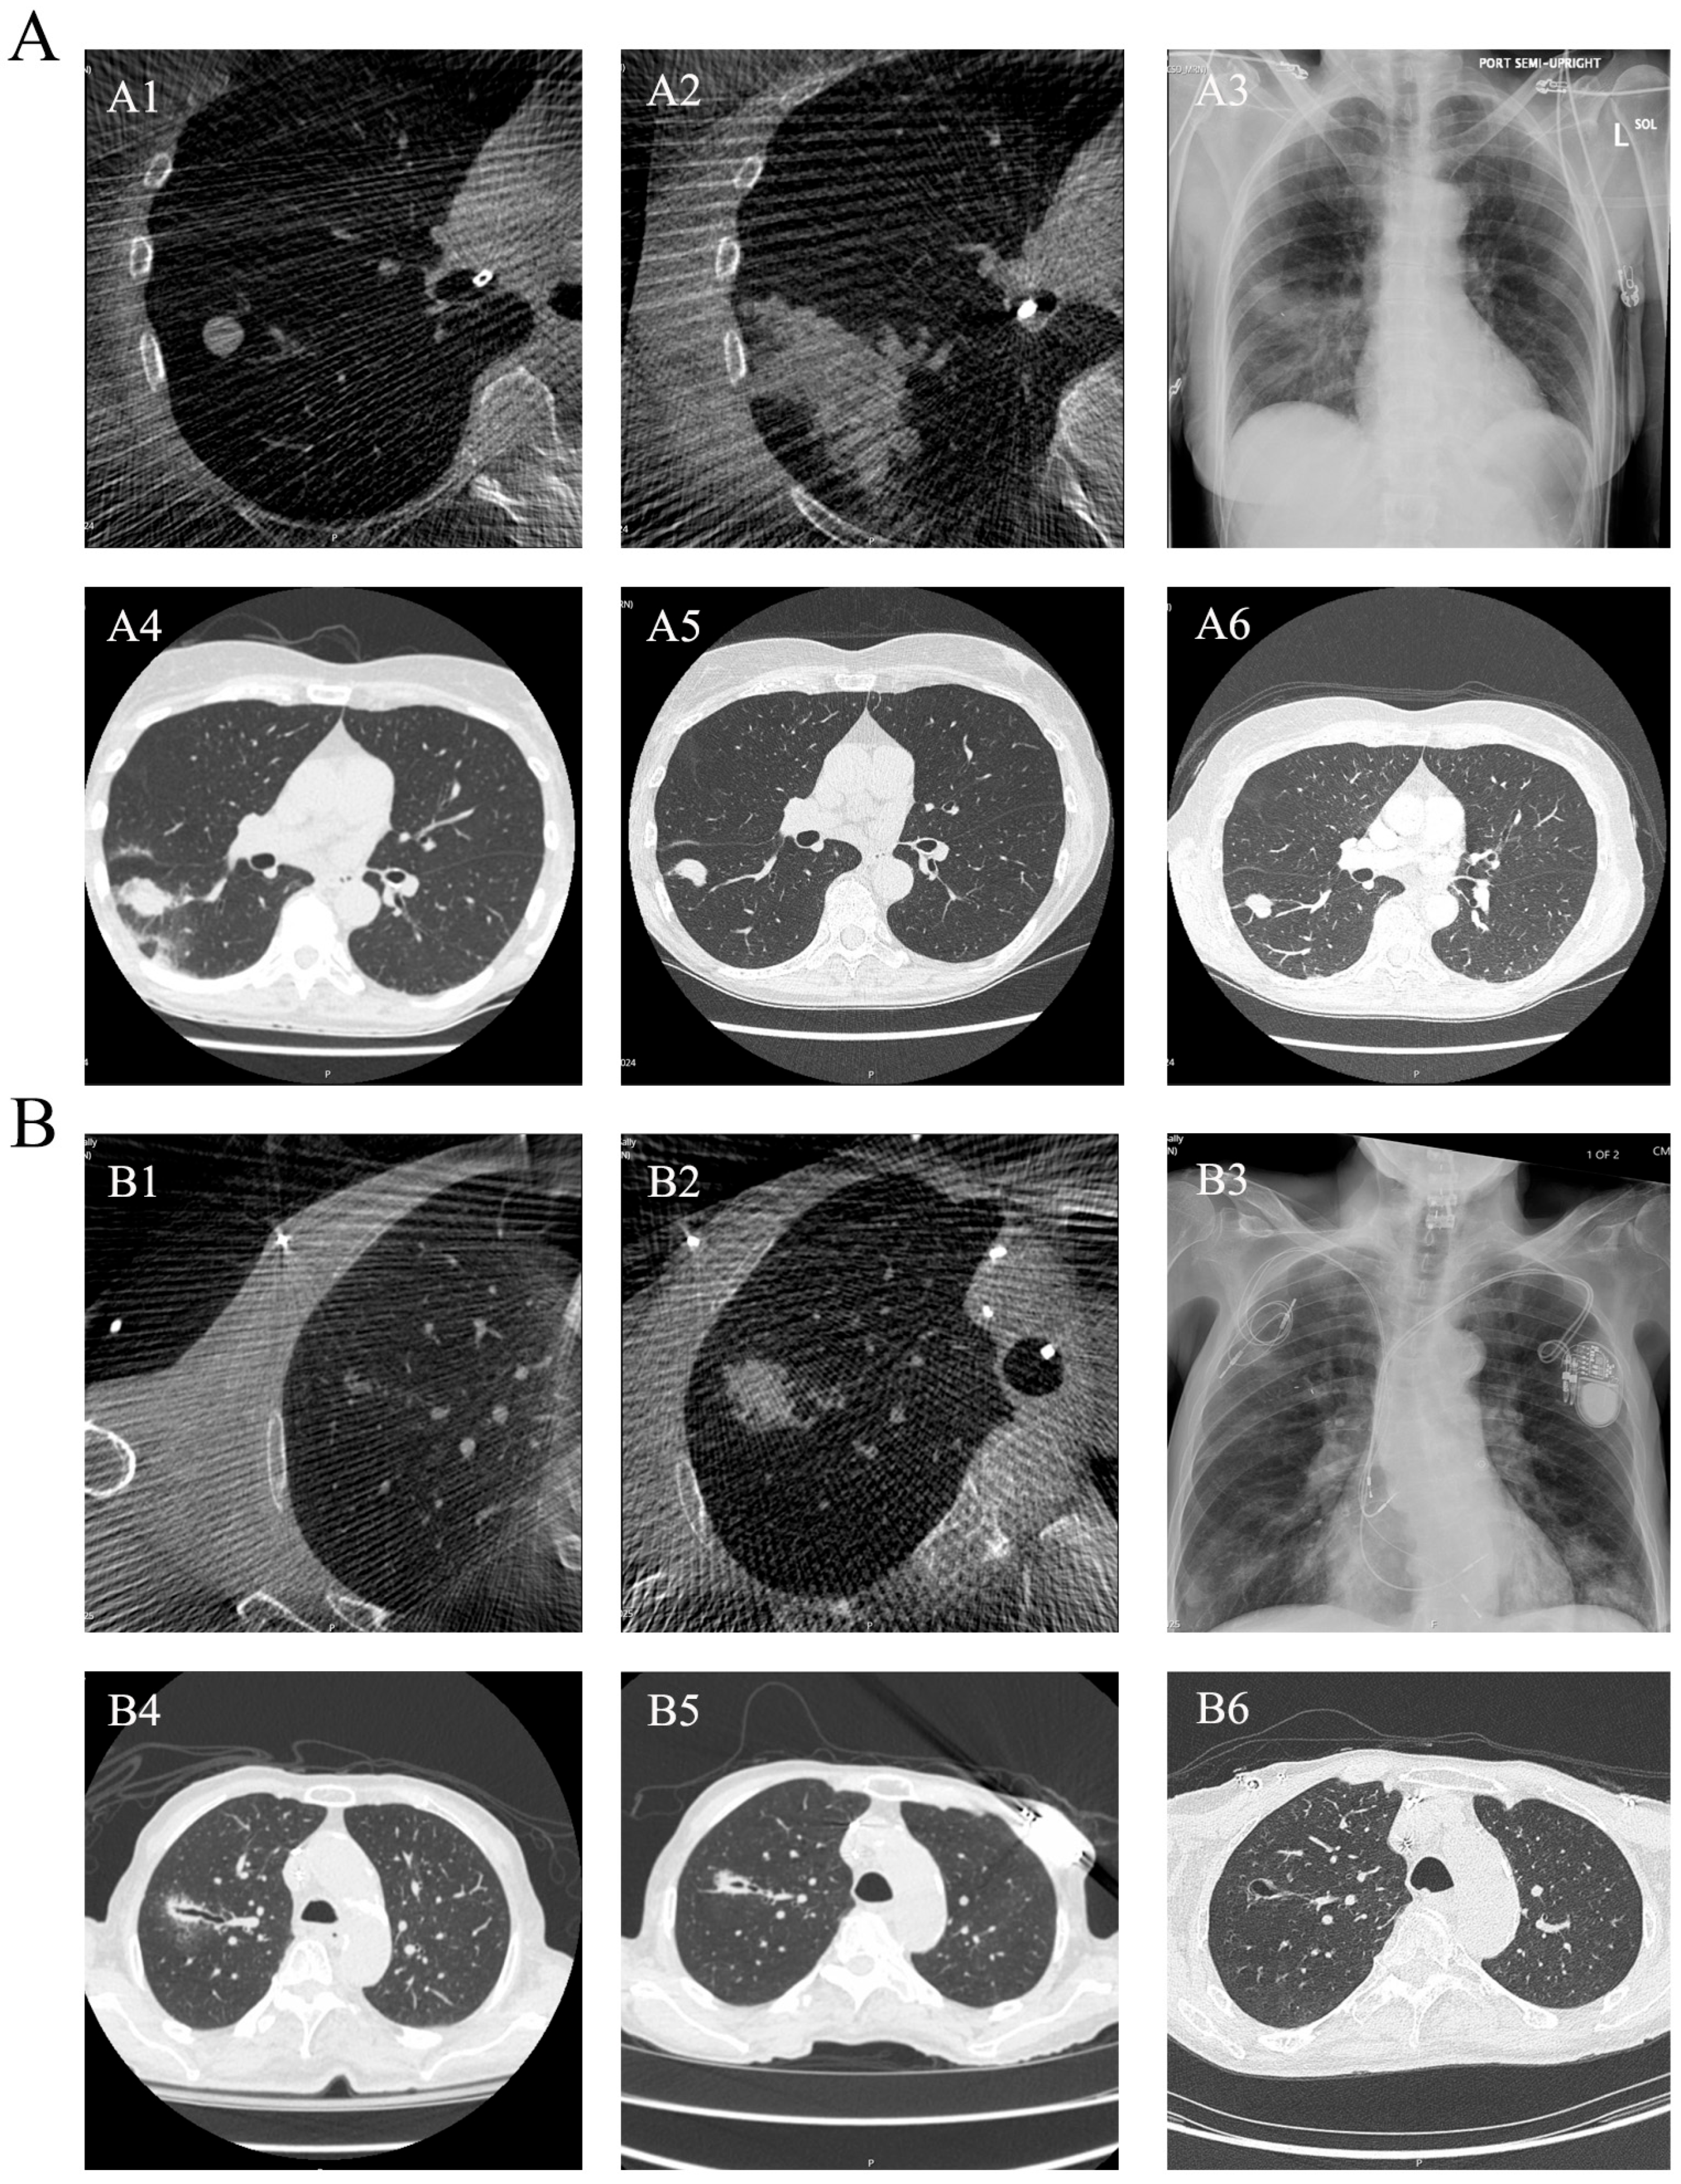

3.2. Technical Outcomes

3.3. Safety and Complications

3.4. Imaging Evolution After Ablation